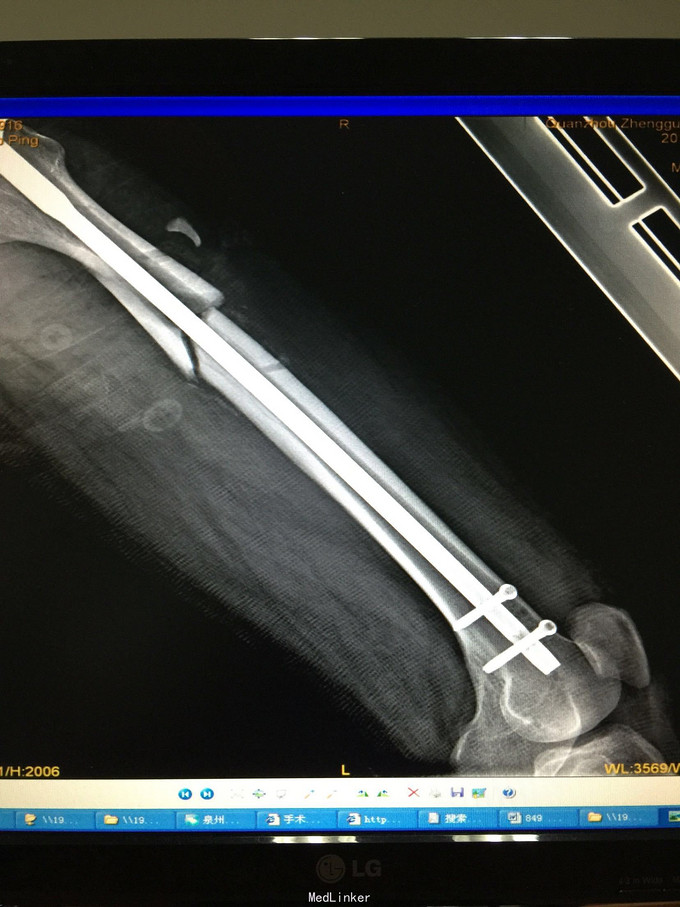

左股骨中上段骨折术后骨不连

诊断:左股骨中上段骨折术后骨不连 处理:左股骨骨折术后骨不连断端清理+防旋钢板内固定+取髂骨植骨术

术后半年 讨论 考虑股骨中上段骨折 应力集中 近段一枚螺钉稳定性不够?